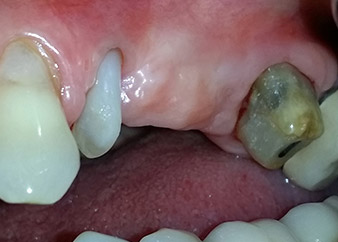

Mujer de 58 años de edad, que además es una apreciada colega y amiga, y se quejaba de dolor y de un aumento en la movilidad del pilar del puente de la pieza dental 24. También había inflamación periodontal, con bolsas de una profundidad de 7 mm en sentido mesiobucal y más de 12 mm en sentido distal, así como furcación de tercer grado. Asimismo, la radiografía reveló una lesión periodontal extensa alrededor de la región apical de la pieza dental 24 (figura 1) tratada previamente con endodoncia (alio loco).

Un año antes, las piezas dentales 25 y 26 se habían extraído por razones traumáticas y endo-periodontales antes de la colocación del puente. Se diagnosticó una lesión endo-periodontal combinada en la pieza dental 24, pero su componente etiológico principal no estaba claro. La paciente declaró su voluntad de mantener el pilar del puente de las piezas 24 y 27 y afirmó que no aceptaría una prótesis extraíble final, ni siquiera provisional. Por lo tanto, se acordó intentar por todos los medios conservar ambos dientes, a pesar del mal pronóstico que mostraban las pruebas radiológicas y clínicas.

Por otro lado, se planificó la colocación de dos implantes sumergidos en las posiciones 25 y 26, en una sesión quirúrgica con desbridamiento periodontal abierto y apicectomía de la pieza dental 24. Debido a la deficiencia ósea vertical del lugar del implante futuro, también se planificó un aumento interno del seno.

Después de la medicación tópica con un 25 % de gel de metronidazol (Elyzol) en las bolsas de la pieza 24, se inició un tratamiento causal de terapia periodontal con desinfección de toda la boca. El tratamiento ortógrado del canal radicular se revisó mediante una obturación con gutapercha termoplástica, un poste de fibra de vidrio y una acumulación de núcleo de composite (figura 2). El puente se recementó fuera de la oclusión para permitir la cicatrización sin problemas de los lugares de la GTR y la GBR.